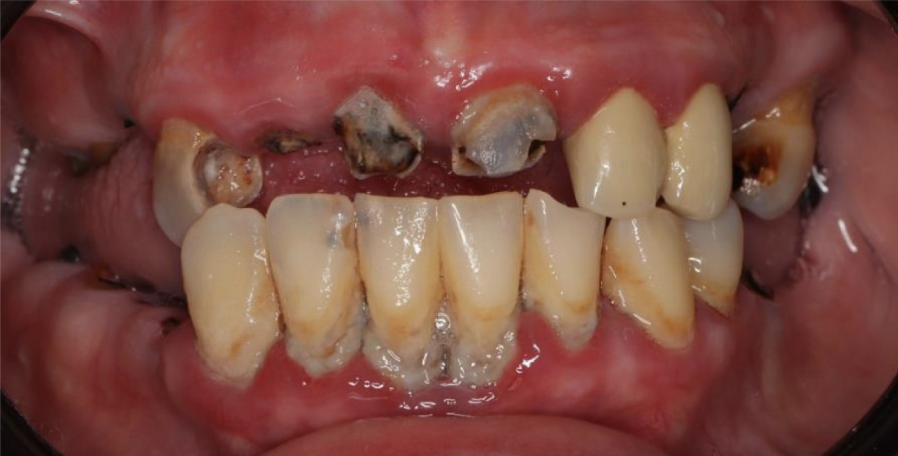

Пациентка обратилась с жалобами на эстетику, затрудненное жевание, отсутствие зубов ну и, конечно, с желанием восстановить долгожданную улыбку.

Было принято решение об удалении всех зубов и восстановлении жевательной и эстетической функции с помощью имплантатов.